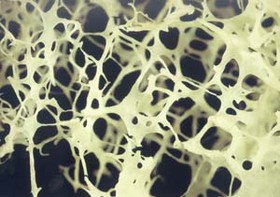

پزشکان پوکی استخوان را بیماری خاموش مینامند که آرام آرام مقاومت استخوانها را از بین میبرد و احتمال شکستگی بالا میرود.

تصویر غذاهای ضدپوکی استخوان کدامند؟این بیماری از سن ۵۰ سالگی به بعد بیشتر خود را نشان میدهد. همچنین در خانمها بعد از یائسگی شتاب بیشتری پیدا میکند.